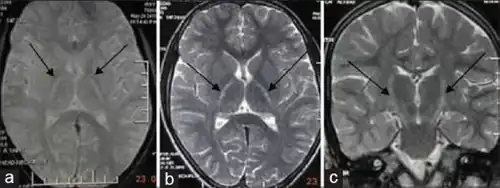

Because symptoms of ALS can be similar to those of a wide variety of other, more treatable diseases or disorders, appropriate tests must be conducted to exclude the possibility of other conditions.[4] One of these tests is electromyography (EMG), a special recording technique that detects electrical activity in muscles.[4] Certain EMG findings can support the diagnosis of ALS.[4] Another common test measures nerve conduction velocity (NCV).[4] Specific abnormalities in the NCV results may suggest, for example, that the person has a form of peripheral neuropathy (damage to peripheral nerves) or myopathy (muscle disease) rather than ALS. While a magnetic resonance imaging (MRI) is often normal in people with early stage ALS, it can reveal evidence of other problems that may be causing the symptoms, such as a spinal cord tumor, multiple sclerosis, a herniated disk in the neck, syringomyelia, or cervical spondylosis.[4]